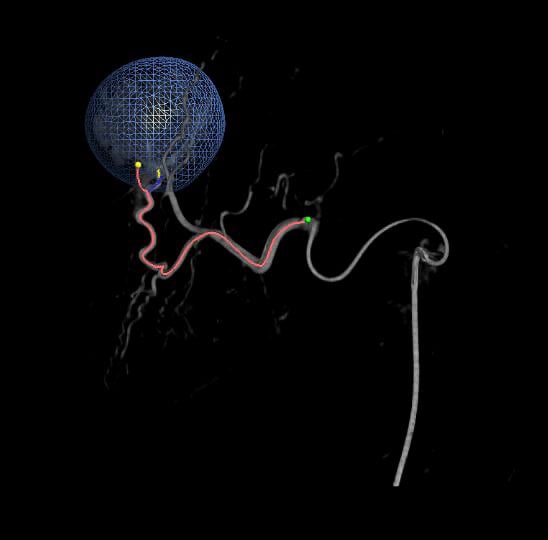

Equipped with sophisticated advanced image-guidance systems and multi-imaging modalities, our physicians may now better visualize and treat patients with complicated diseases. This system includes technology to make this easier in both 2D and 3D with dose reduction technology. It is equipped with integrated Intravascular Ultrasound. Vessel Navigation guidance, 2D Vessel Perfusion, 3D roadmap and Vessel quantitative measurements are offered as well. Vessel Navigator allows reuse of 3D vascular anatomical information from existing CTA and MRA datasets as a 3D roadmap overlay on live X-ray images. With its sophisticated visualization, it provides an intuitive and continuous 3D roadmap to guide you through vasculature during the entire procedure. The system is connected to our PACS system allowing us to visualize previous diagnostic images inside the room.